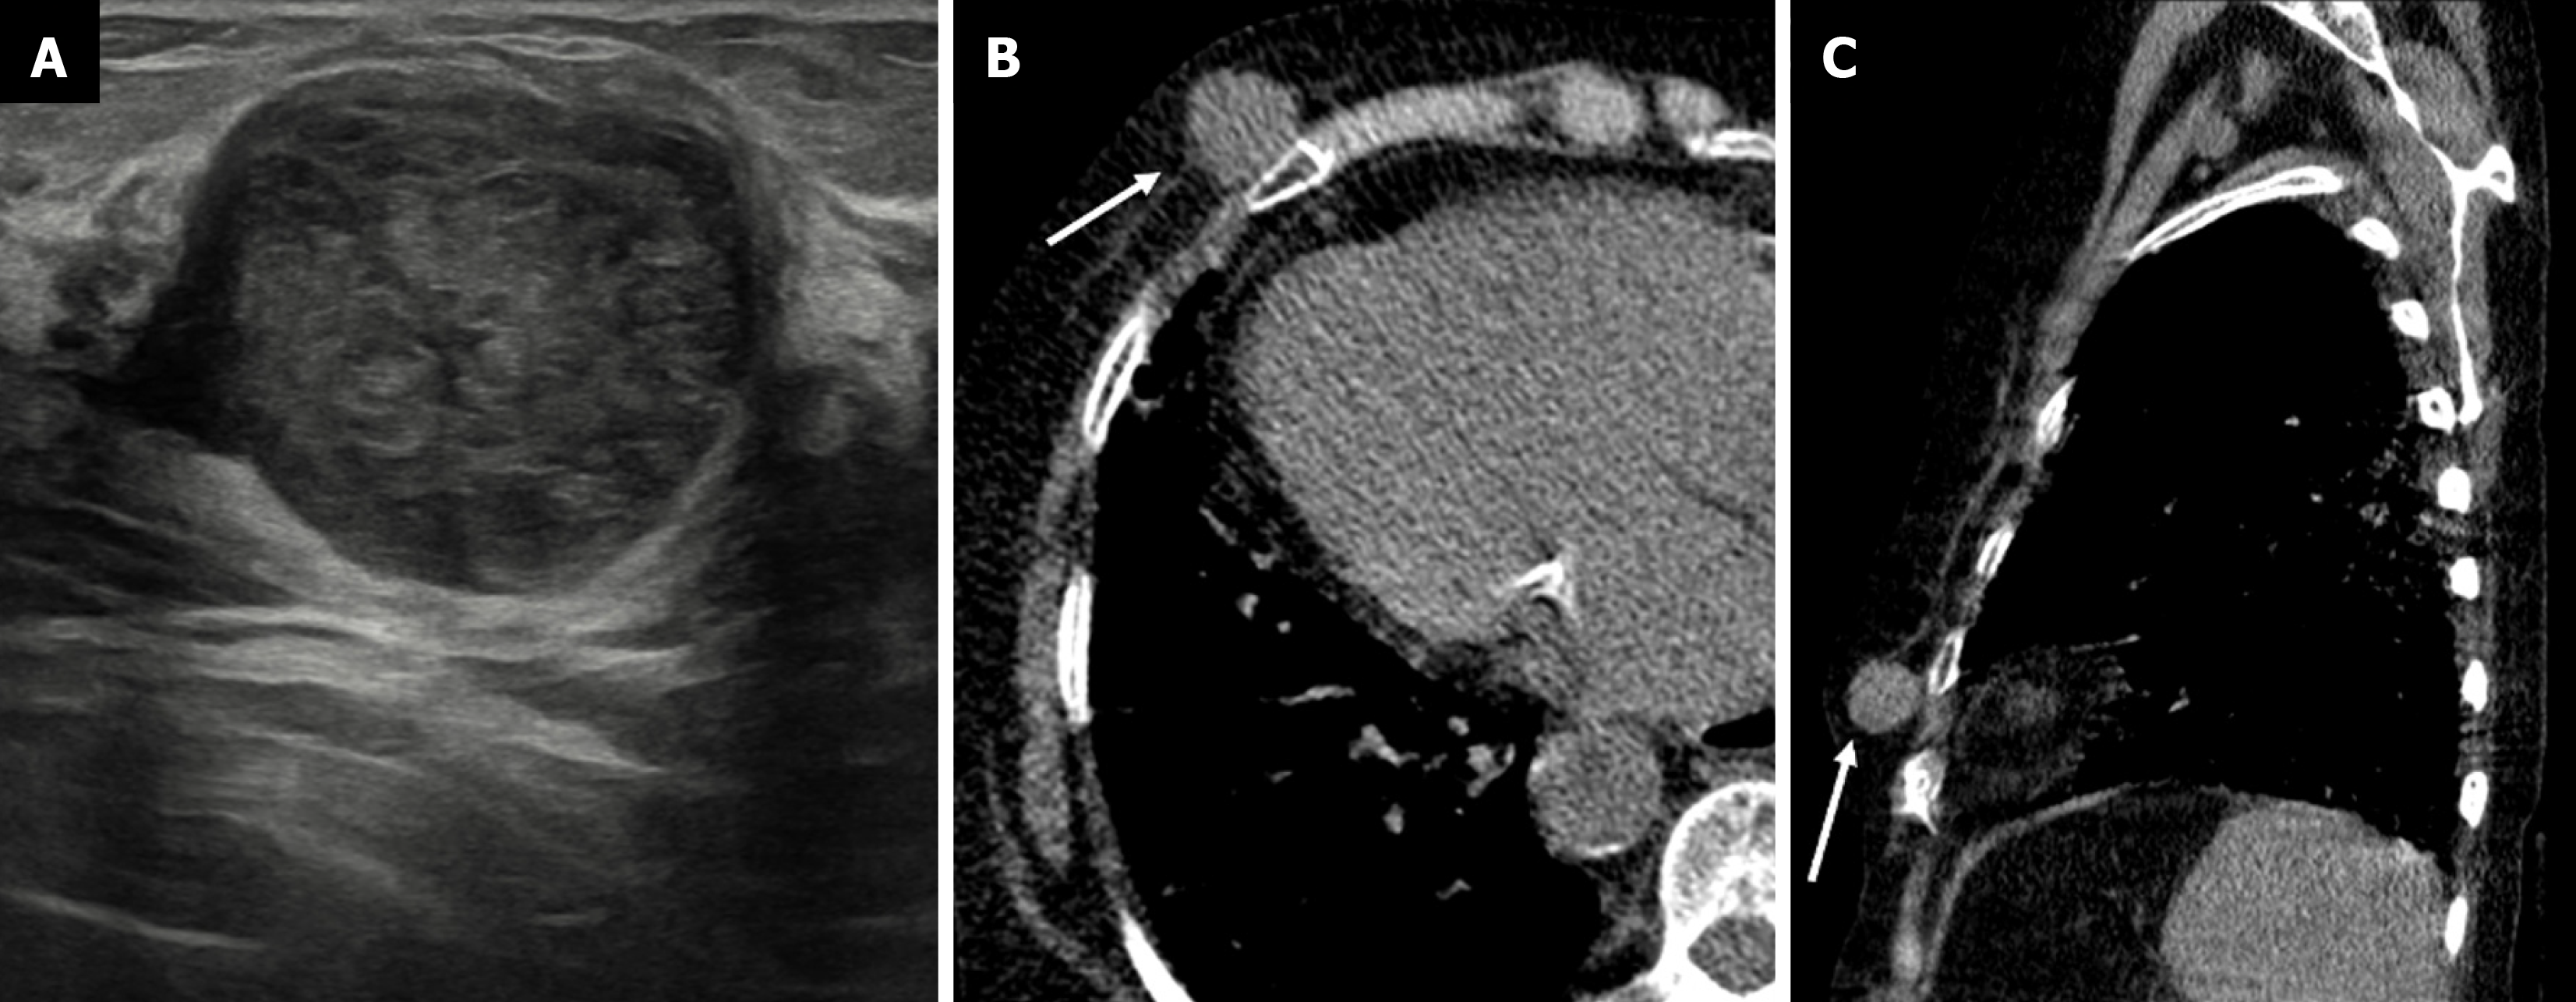

Figure 16  Myofibroblastoma in a 56-year-old male with a palpable mass in the right breast.

A: Ultrasound image showing a round circumscribed heterogeneously hypoechoic mass; B: Axial; C: Sagittal noncontrast computed tomography sections demonstrating a well-defined hypoattenuating soft tissue density mass in the right breast (white arrows) with no calcifications or chest wall invasion.